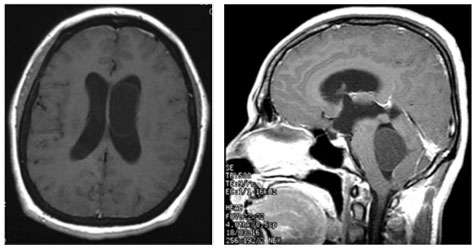

- When cysticercosis affects the brain or spinal cord, the condition is called neurocysticercosis. Usually, the cyst causes inflammation in the brain tissue itself which results in a seizure. In about 10% of neurocysticercosis cases, the cysts are found within the cerebral ventricles or in the cerebrospinal fluid spaces (cisterns). This can cause hydrocephalus or symptoms due to pressure on the brain.

- In about 10 percent of neurocysticercosis cases the cysts are found within the cerebral ventricles or in the cerebrospinal fluid spaces (cisterns). This can cause hydrocephalus or symptoms due to pressure on the brain.

- Diagnosis is best made by magnetic response imaging (MRI), although intraventricular cysts can sometimes be very difficult to detect on routine MRI imaging.